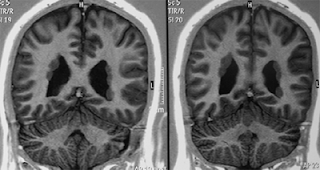

La resonancia magnética (RMI) del cerebro en el SED generalmente no presenta nada fuera de lo común en cuanto a anomalías estructurales importantes. Por ello, con la excepción de las presentaciones agudas en las que se sospecha enfermedad cerebrovascular, dicha investigación generalmente no forma parte de la evaluación basal de los pacientes con SED. Sin embargo, la presencia de un caso claro de transmisión dominante ligada al cromosoma X, y/o la coexistencia de convulsiones, debería apuntar a la exclusión de la forma rara del SED con heterotopia periventricular (Figura 2), debida a menudo a mutaciones en FLNA (76, 77).

Figura 2. Heterotopia periventricular en una mujer de 37 años con características del Síndrome de Ehlers-Danlos tipo Clásico

Registros aislados asocian el SED con polimicrogiria (78), agenesia del cuerpo calloso (79), dilatación del 4to ventrículo, de la cisterna supracerebelosa y del ventrículo lateral, o agrandamiento desproporcionado del cuerno anterior del ventrículo lateral (80), pero no se ha confirmado la consistencia de estas asociaciones.